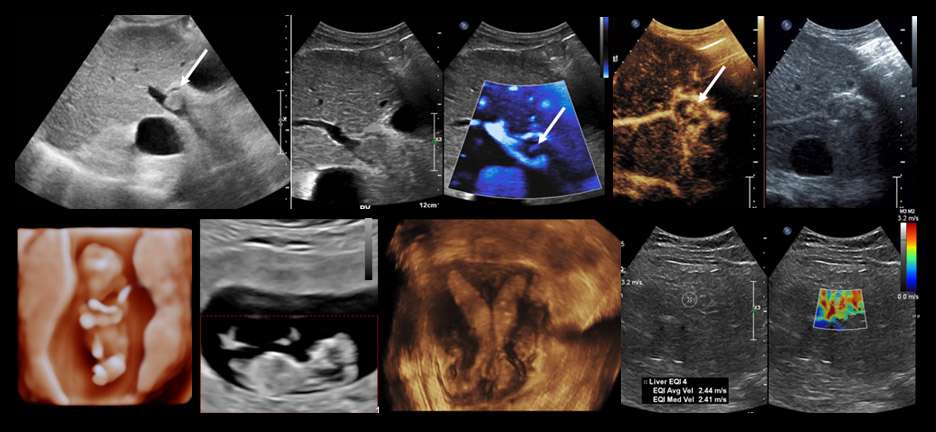

UCLA Health Ultrasonography serves the Los Angeles area with the full array of ultrasound procedures, including general abdominal, gynecologic-obstetric-fetal, urologic, head-neck-thyroid and vascular examinations. Our specialists use the most advanced techniques, including color-flow Doppler and superb microvascular imaging, 3-D ultrasound, shear-wave elastography, and contrast enhanced ultrasound.

Ultrasound directed procedures including biopsies, aspirations and saline infusion sonohysterograms are performed in our outpatient centers. All ultrasound facilities are equipped with high resolution 2-D grayscale and color-flow Doppler scanning equipment applying the latest software platform where available. Our specialists also conduct ongoing research in many projects including application of artificial intelligence technologies in image analysis.